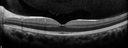

Chronic Endophthalmitis and Cystoid Macular Edema408 viewsVA 20/50 - Culture negative. Cleared with intravitreal antibiotics and decadronNov 14, 2019